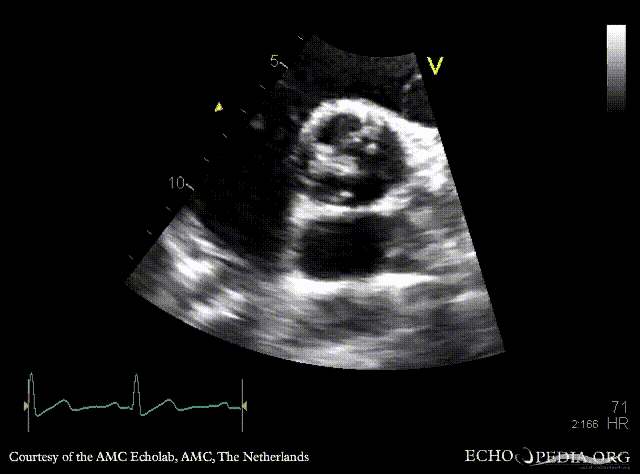

E00855.gif E00856.gif

PSAX: bicuspid aortic valve PSAX with Color Doppler: severe aortic regurgitation